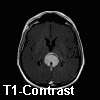

Imaging of the Case: MRI demonstrated a 4.4 x 3.5 x 4.7 cm mass in the pineal region. The lesion is isointense on T1 with homogeneous post contrast enhancement (Panel A) and slightly hyperintense on T2. The tumor is relatively well demarcated. The tectal plate is not visualized and mass effect is demonstrated upon the third ventricle outflow tract and midbrain. A second but smaller lesion of similar imaging characteristic is dmonstrated in the suprasellar region involving the optic chiasma. There is also mild hydrocephalus. CT scan (Panel B) demonstrated also a similar enhancing lesion. Calcifications are demonstrated on both MRI and CT scan.